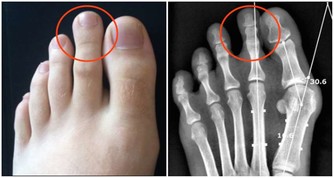

它可以保護您的細胞免受損害和感染,並保持甲狀腺正常運轉。硒還可以保持肌肉強壯,並可以幫助預防與年齡相關的疾病,例如癡呆,某些類型的癌症和甲狀腺疾病。每天只吃一兩個巴西堅果就足夠了。不要過多,因為硒過多會使頭髮掉落並使指甲變脆。